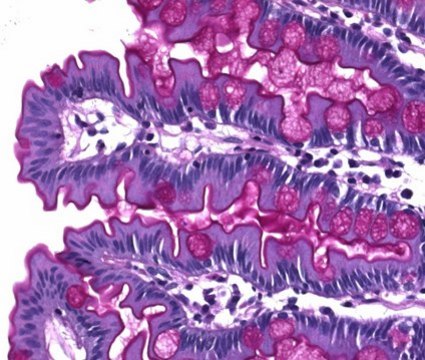

For microscopy. Ready-to-use staining solution for human-medical cell diagnosis.

Schiff‘s reagent -for microscopy for the periodic acid Schiff, or PAS reaction, is a ready-to-use solution used for the detection of mucopolysaccharides, glycogen, muco- and glycoproteins, glyco-, phospholipids, basal membranes and collagen. The PAS (periodic acid Schiff) reaction is one of the most frequently used chemical methods for the detection of aldehyde and mucosubstances in histology. In the PAS reaction, the histological specimen material is first treated with periodic acid, resulting in the oxidation of the 1,2-glycols into aldehyde groups. The addition of Schiff′s reagent (fuchsin-sulfuric acid) in the second step causes the aldehydes to react to form a brilliant red color. In the end result, the PAS reaction yields a specific color reaction with unsubstituted polysaccharides, neutral mucopolysaccharides, muco- and glycoproteins, and glyco- and phospholipids. The PAS reaction can be further combined with the Alcian blue staining method to detect mucosubstances (glycosaminoglycans). 500 ml are sufficient for approx. 2500 - 3000 stainings. It is registered as IVD and CE certified product and can be used for clinical diagnostics. For more details, please see instructions for use (IFU). The IFU can be downloaded from this webpage.